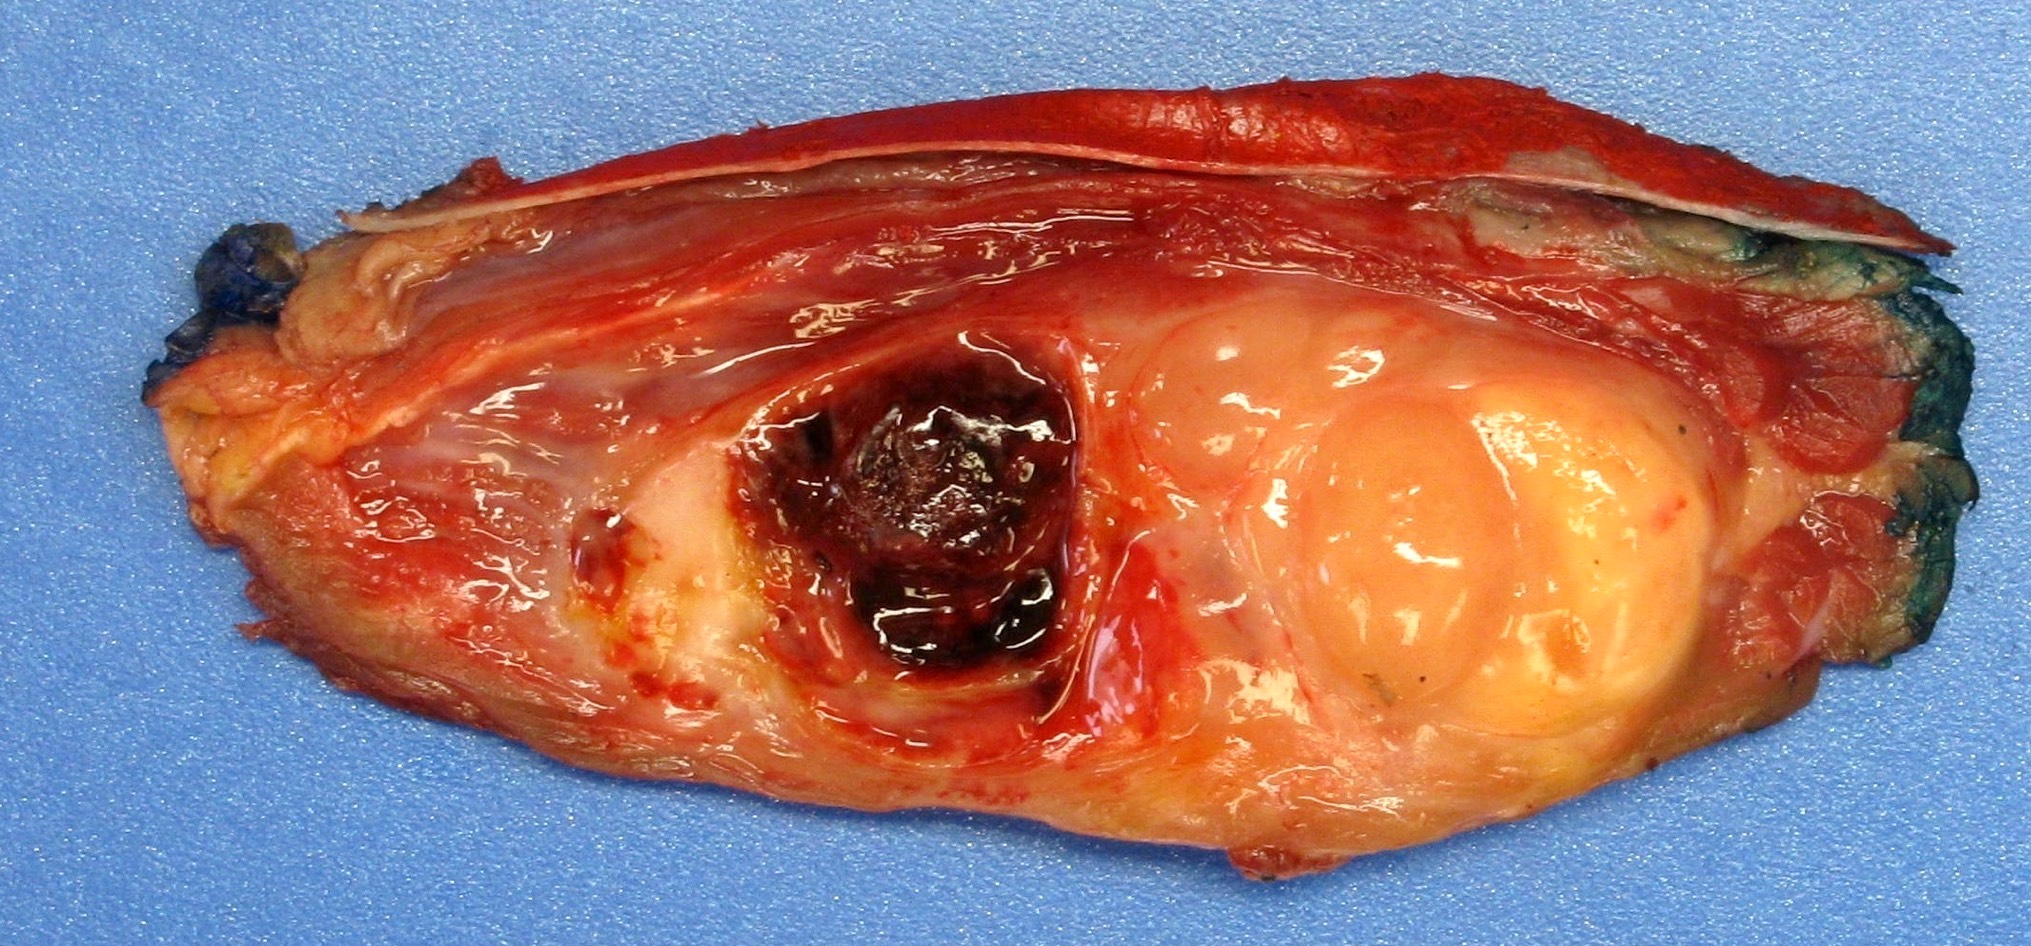

Gross description

- Can be variable in size (median 8 cm, range from 1 - 30 cm) (Am J Surg Pathol 2009;33:1850)

- Cut surface with variable hemorrhage and necrosis

- Appears circumscribed, often in deep soft tissue and involving striated muscle (Am J Surg Pathol 2009;33:1850)

Gross images